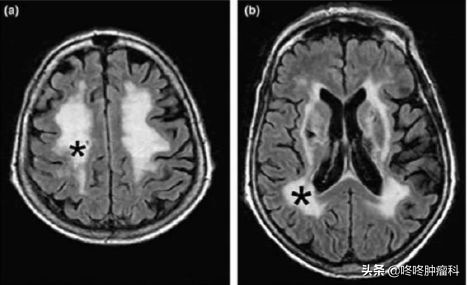

此外,该研究团队还在部分患者的脑部MRI片子上看到了服药一段时间后,脑白质区域出现了明显的异常信号(下图黑色*符号圈出了具体位置)。